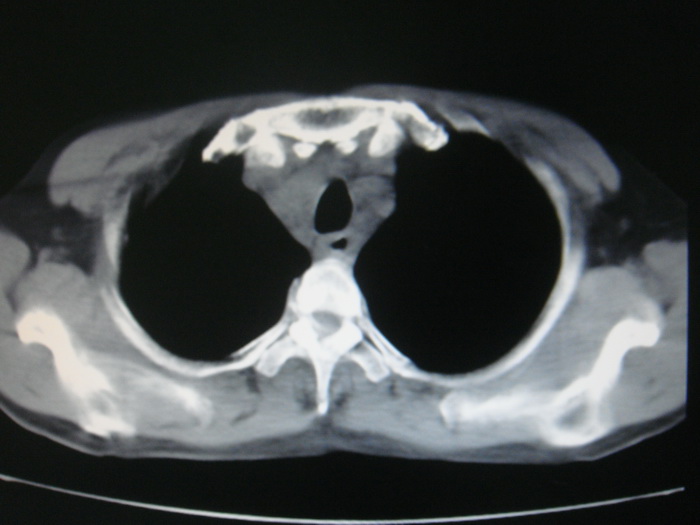

标题: CT28366:男性,45岁,偶尔发现右颈部肿块行胸部CT扫描。 [打印本页]

男性,45岁,偶尔发现右颈部肿块行胸部ct扫描。

两肺多发结节灶及纵膈淋巴结肿大考虑为转移

两肺多发性转移瘤,纵隔淋巴结转移。

两肺多发性转移瘤,纵隔淋巴结转移。食道中上段管壁似乎增厚,作相关检查。

两肺多发性转移瘤,前上纵隔淋巴结转移。